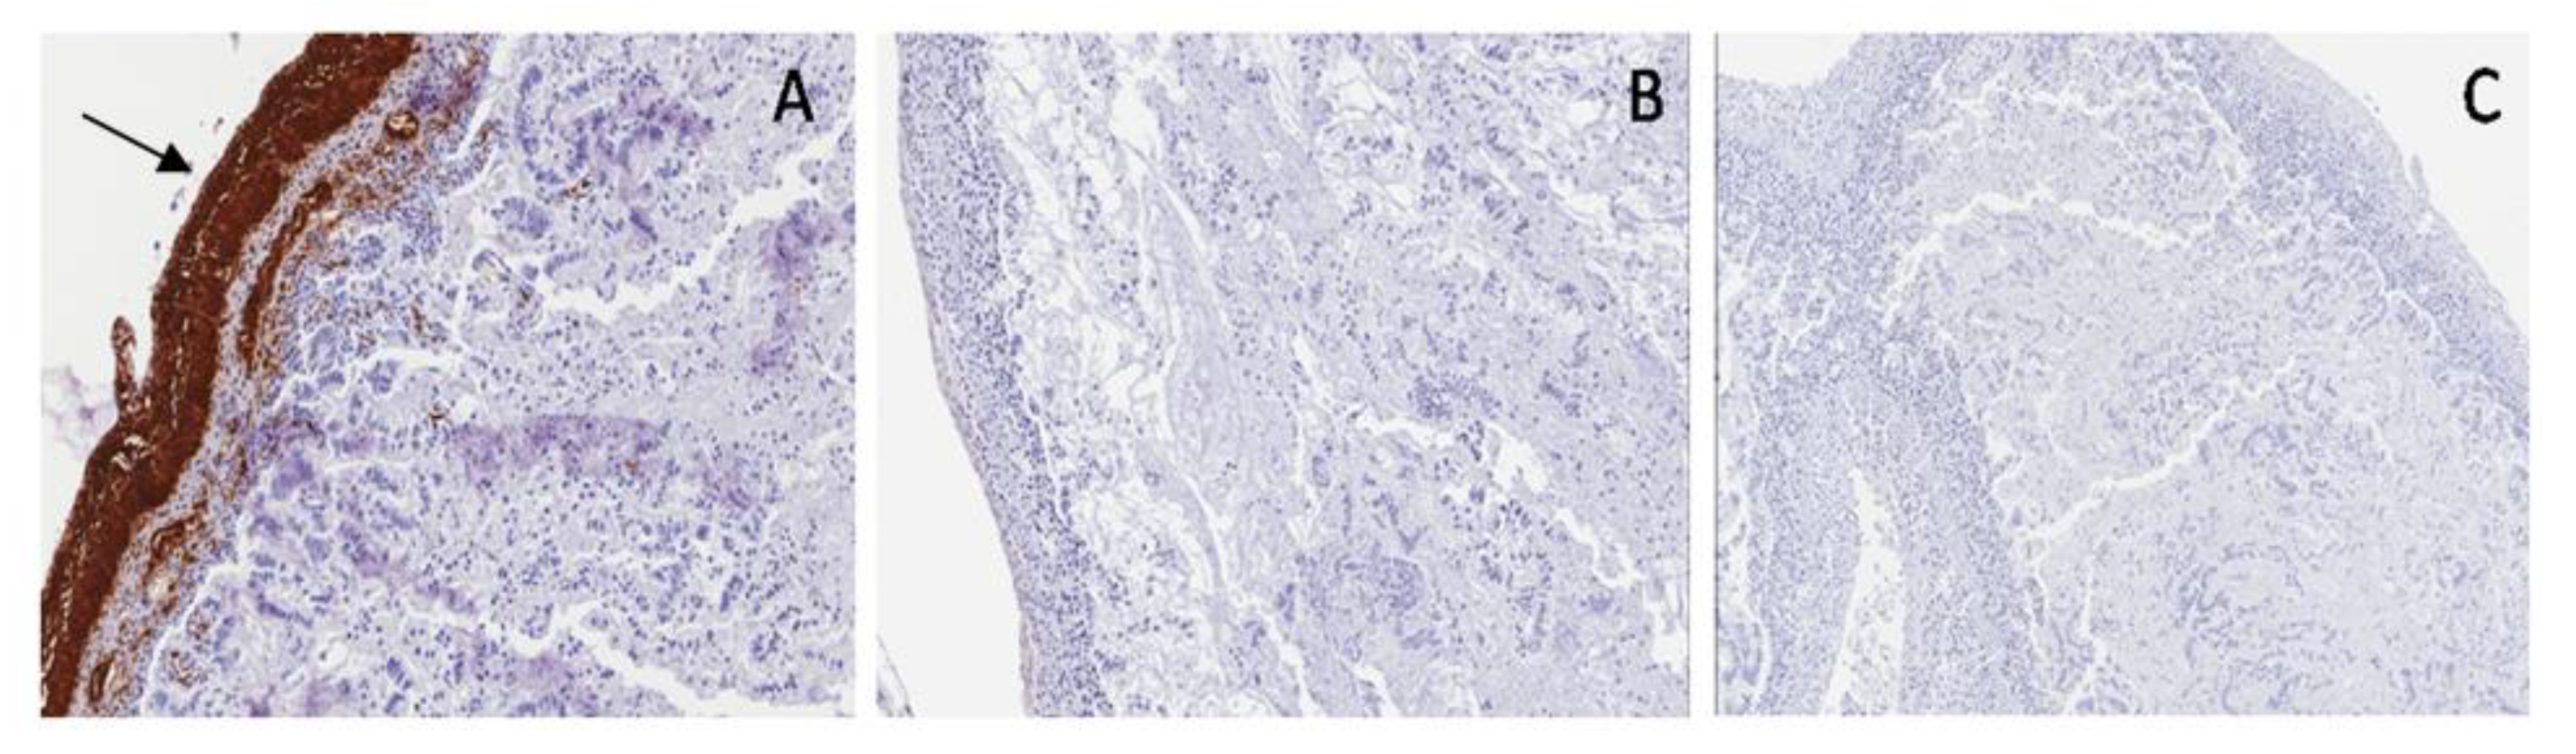

Bladder: SMA highlighted a thin, longitudinal, muscular layer with disarray of muscular fibers (shredded-carrots-like) and poor interposed embryonal mesenchyme; S100 was shown only in peripheral nervous fibers and WT1c was negative (Figure 7).

Figure 7. Case 2, Prune-Belly syndrome (PBS). Immunohistochemical staining in bladder: SMA (A) in a thin, longitudinal, muscular layer (arrow), S100 (B) only in peripheral nervous fibers (arrow), WT1c (C) negative.